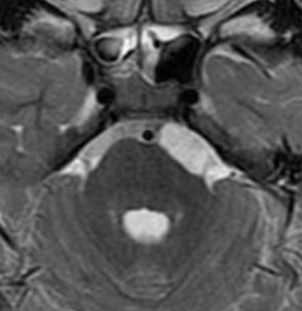

Порэнцефалические кисты проявляются в виде интракраниальных кист с кхорошо очерченными краями и центральной плотностью, соответствующей таковой для ЦСЖ. Не наблюдается масс-эффекта на прилежащую паренхиму, хотя кисты большого размера могут оказывать локальное воздействие. Порэнцефалические кисты не имеют солидного компонента и не накапливают контрастное вещество.

Как и на КТ, порэнцефалические кисты хорошо визуализируются при МРТ, и часто их локализация соответствует сосудистой территории. Кисты ограничены белым веществом головного мозга, в котором может наблюдаться глиоз (как говорилось выше, это зависит от период, в котором произошел инсульт; чаще наблюдается в семейных случаях). Еще раз стоить отметить, что поверхность кисты не выстилается серым веществом, что характерно для арахноидальных кист и шизэнцефалии. Обычно кисты сообщаются с желудочковой системой и/или субарахноидальным пространством.

Содержимое кист по сигнальным характеристикам идентично таковым для ЦСЖ:

- Т1: гипоинтенсивное;

- Т2: гиперинтенсивное;

- FLAIR: подавление сигнала содержимого;

- DWI: нет рестрикции диффузии;

Порэнцефалические кисты - врождённые кисты различной этиологии, локализующиеся в паренхиме мозга или в области сосудистого сплетения желудочков.При МРТ головного мозга они обычно округлые, с гладкими стенками. Очень часто такие кисты сочетаются с аномалиями развития: отсутствием прозрачной перегородки и полимикрогирией. Содержимое порэнцефалической кисты при МРТ головного мозга ликворное, иногда с небольшой примесью белка.